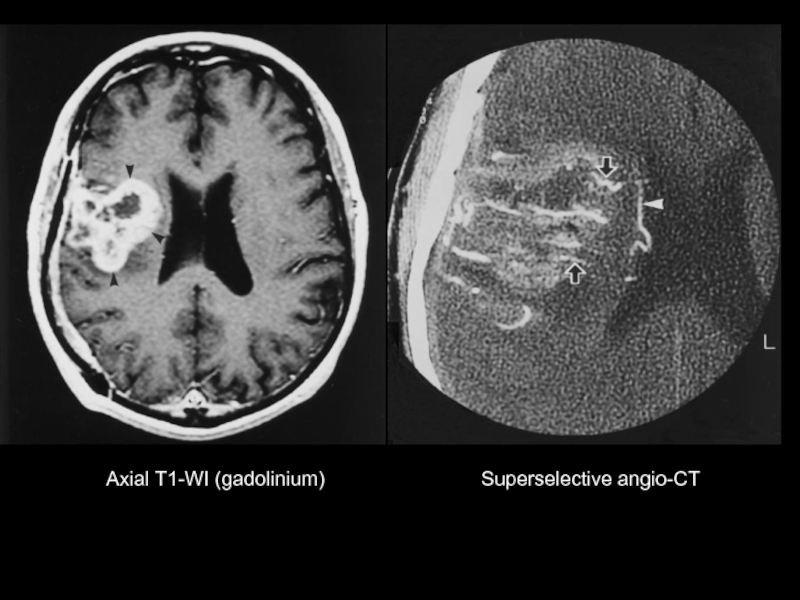

Axial T1-WI (gadolinium)

Axial FLAIR

Superselective angio-CT